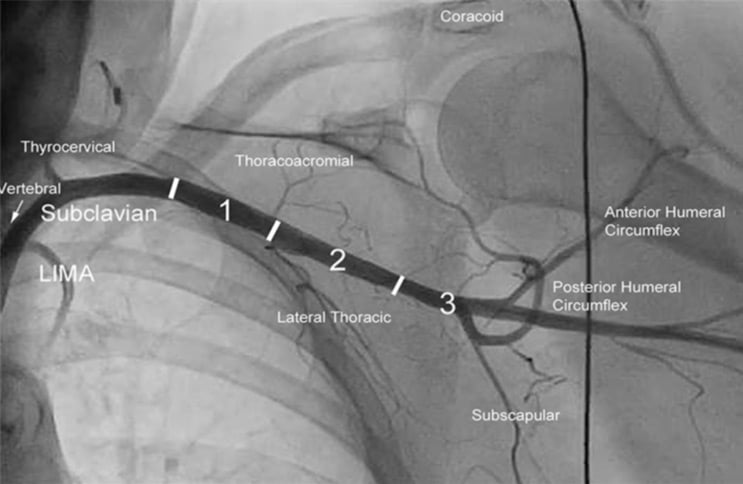

- Prefer left axillary in most cases for a more favorable orientation to the aortic valve; reserve the right axillary artery for cases where the left is unsuitable (Figures 1- 5).

Figure 2: Axillary artery segmentation

Figure 3: Reference collateral arteries